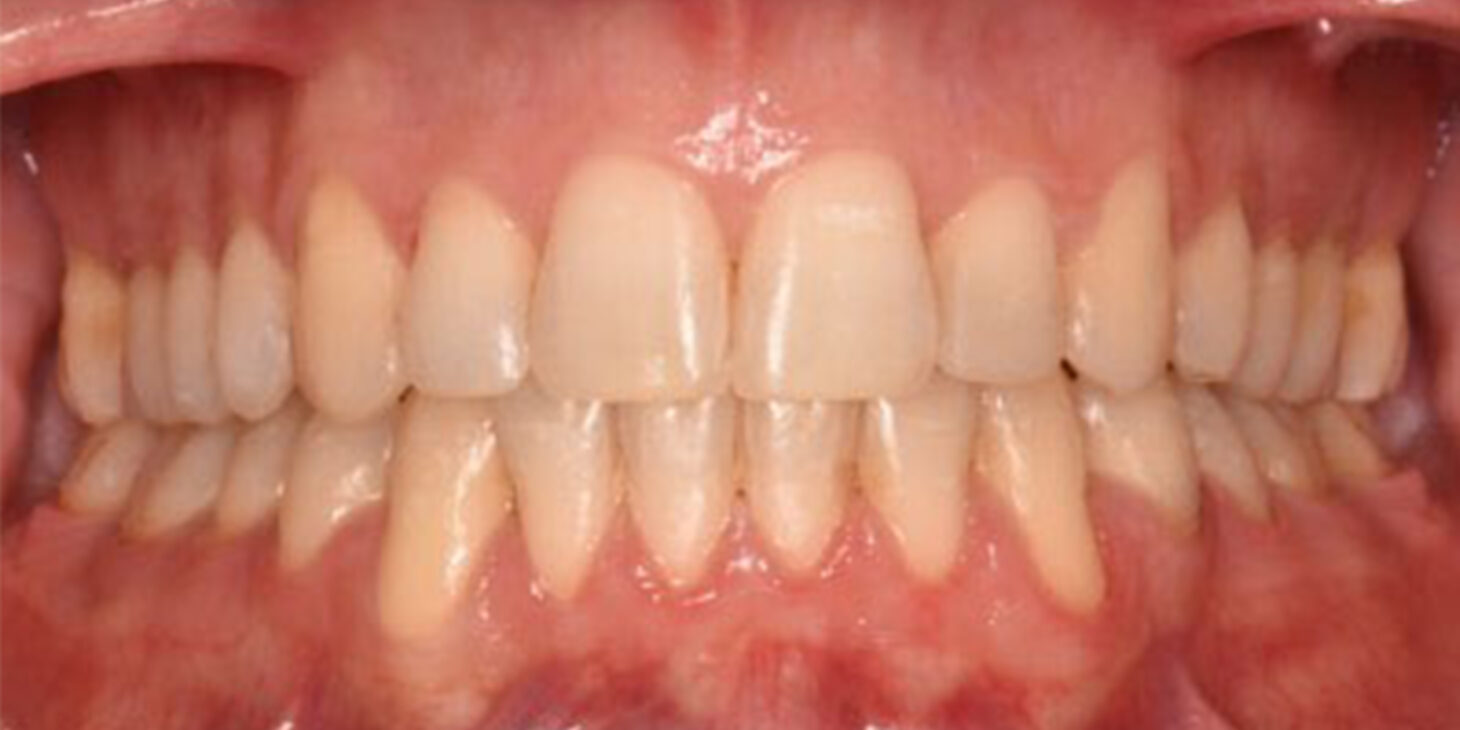

A 38-year-old male patient sought orthodontic treatment with both functional and esthetic concerns. His main complaints included the appearance of an inverted smile arc, reduced incisor display, and a general lack of harmony in his smile.

The extraoral examination revealed a long facial type with an increased lower facial third, nasolabial folds accentuated by insufficient midface support, and broad buccal corridors due to maxillary compression. Intraoral analysis showed a posterior crossbite, negative torque on posterior teeth, and an altered occlusal balance. Radiographic and cephalometric evaluation confirmed the clinical findings, with an increased mandibularplane angle and mandibular posterior rotation. This rotation contributed to a convexity of +4 mm, although the underlying problem was a retruded maxilla with insufficient midface support. Vertical facial height was also increased. Importantly, the temporomandibular joint evaluation showed a posterior condylar position with intact cortical bone, no pain, and no joint sounds.

(Images: Intraoral Initial)